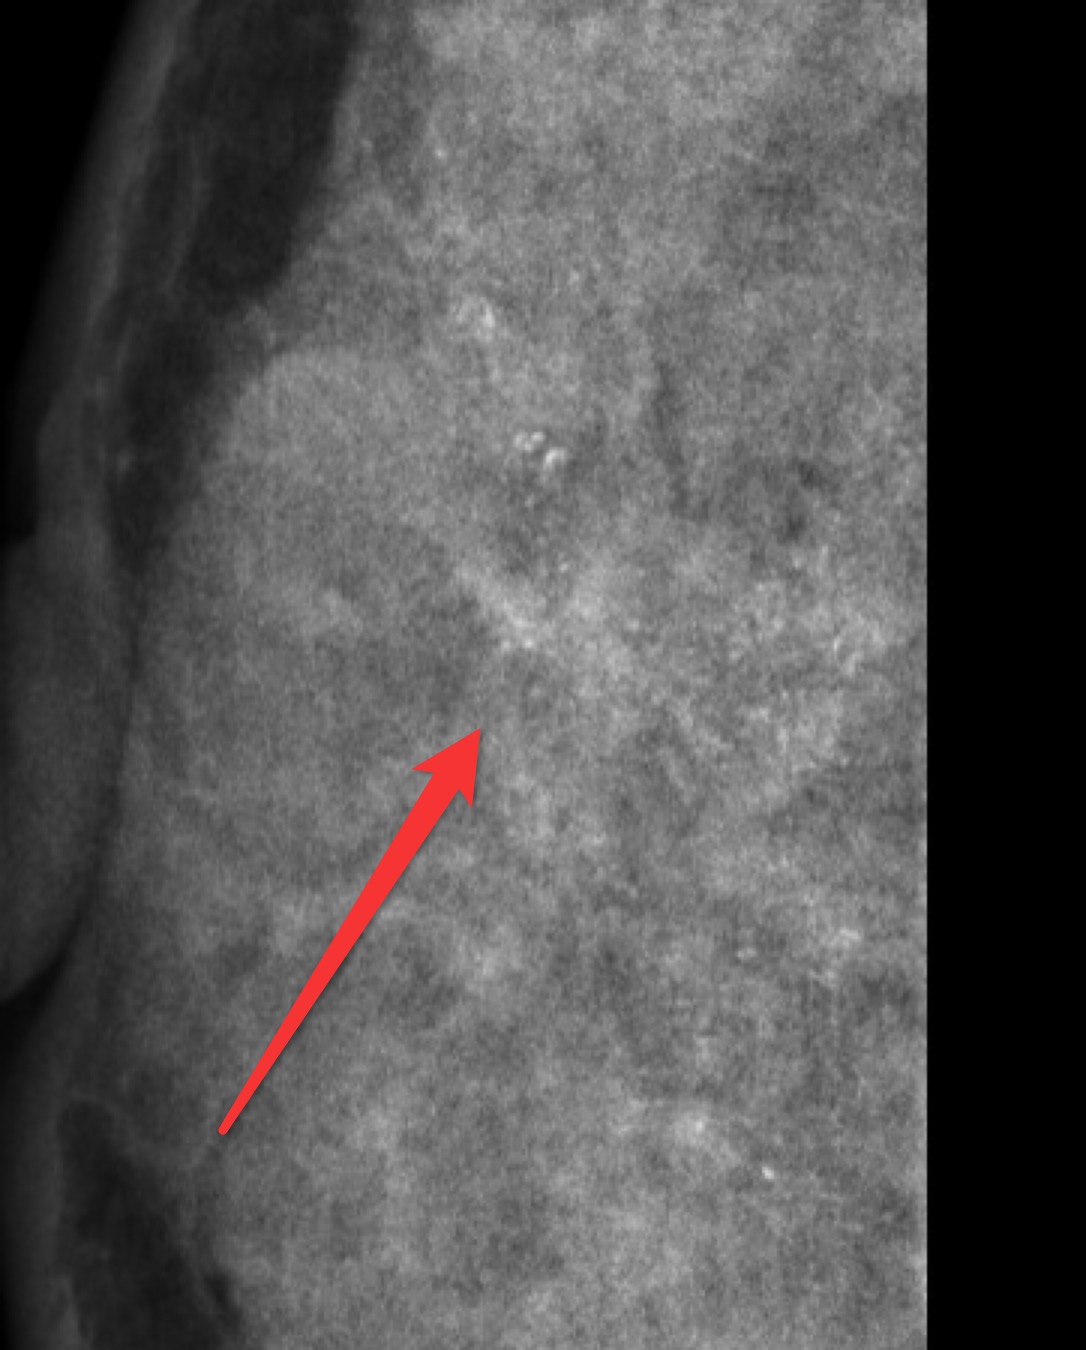

它怕“小透明”。 B超对某些类型的癌不敏感,比如那种只在导管内密密麻麻长着微小钙化的原位癌。那些钙化点像针尖一样小,B超的“相机”分辨率不够,拍不清楚。这时候,就得请出另一位侦探——乳腺钼靶,它可是捕捉钙化的专家。所以有时候要“组合出警”,才能不放过坏蛋[2]。

行钼靶检查提示为异常钙化(见标记处),BI-RADS分级4类,穿刺病理证实为恶性。